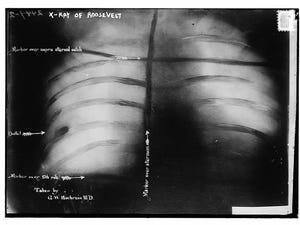

Không chịu nổi dằn vặt từ ác mộng, Schrank lên đường thủ tiêu Roosevelt vào ngày 14/10/1912 tại Milwaukee, Wisconsin. Chẳng ngờ, lần đột kích này đã khiến tên tuổi của vị Tổng thống đời thứ 26 càng thêm vang dội trong sử sách. Vừa dợm bước ra khỏi khách sạn Gilpatrick (nay đã đổi tên thành khách sạn Hyatt) để diễn thuyết tại Thính phòng Milwaukee, ngực Roosevelt đã trúng phải viên đạn từ nòng súng của Schrank. May mắn thay, trong túi áo trước ngực ông lúc này đang chứa xấp diễn văn dày tận 50 trang, bên cạnh hộp đựng kính bằng kim loại. Chính hai vật này đã giảm uy lực của viên đạn, cứu mạng vị Tổng thống thứ 26 của nước Mỹ.

Kỳ diệu thay, dù mấy phút trước suýt nữa đặt chân vào cửa tử nhưng ông vẫn điềm nhiên hoàn thành bài diễn thuyết dài 84 phút trước mặt đông đảo cử tri. Trước khi bắt đầu, Roosevelt bình thản báo tin dữ cho mọi người: “Xin quý vị giữ im lặng cho. Tôi không rõ liệu mọi người có biết tôi vừa bị bắn không, nhưng người của Đảng Bull Moose không dễ đánh bại như thế. Nhờ có xấp diễn văn trước ngực mà tôi có thể bảo toàn tính mạng, song trong lúc nghe phát biểu, các vị có thể thấy trên ngực tôi bị thủng một lỗ - đó chính là nơi viên đạn xuyên qua, dù không găm thẳng vào tim. Vì viên đạn đang ở trong cơ thể nên tôi không sao nói quá lâu, nhưng tôi sẽ cố gắng hết sức”.

Dù việc kiên trì phát biểu đã củng cố uy tín của Roosevelt, song ông không trụ nổi trong những tuần cuối cùng diễn ra cuộc tranh cử. Tuy có được nhiều phiếu bầu nhất từ bên thứ ba, nhưng ông buộc phải phân chia số phiếu thuộc Đảng Cộng hòa với đối thủ William Taft. Đối với người dân Mỹ, Roosevelt khi ấy tồn tại như một huyền thoại sống, mà huyền thoại thì chiến tích có huy hoàng cách mấy cũng vô tình bị xem là lẽ đương nhiên. Cuối cùng, vị trí Tổng thống thuộc về Taft. Về phần Roosevelt, ông phải mang theo viên đạn từ họng súng của kẻ ám sát mãi cho đến khi qua đời vào năm 1919, bởi theo lời bác sĩ, viên đạn ấy sẽ gây nguy hiểm cho ông nếu cố chấp lấy ra.